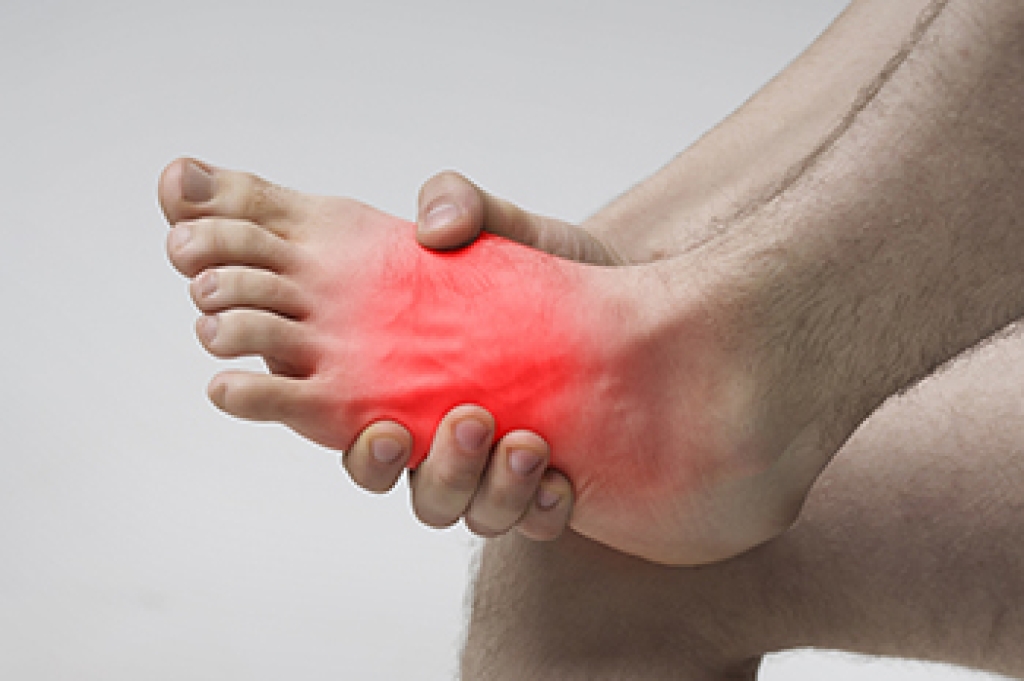

Your feet are a critical part of your overall health, and our podiatry services focus on diagnosing and treating disorders of the lower extremity to ensure your feet remain healthy and functional. We provide diabetic foot care and treat a range of issues, including foot and heel pain, bunions, hammertoes, fungal nails, plantar fasciitis, ingrown toenails, ankle pains, varicose veins, and leg swelling. We use advanced surgical techniques to correct foot problems and minimize scarring, specializing in bunion and hammertoe surgery, as well as Achilles' tendon repair.

Enhance your appearance and boost your confidence with our body sculpting services, including body contouring, cellulite reduction, fat reduction, and feminine rejuvenation injectables. Understanding the importance of foot health, we emphasize the connection between foot issues and overall well-being. For instance, a swollen foot can indicate heart problems, while pins and needles may signal diabetes or nerve issues. We address the structural aspects of the foot that impact posture and balance, reducing the risk of falls.

Make foot care an integral part of your health regimen. If you notice any unusual symptoms in your feet or require comprehensive health services, please contact us. Trust our experienced team to provide the care you need.